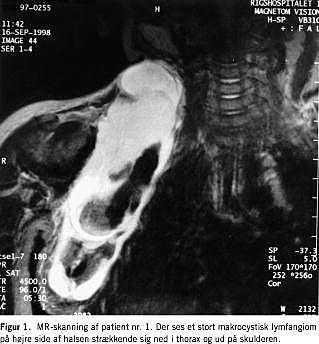

Patienterne blev før behandling udredt rutinemæssigt med UL- og CT/MR-skanning, (Figur 1 ), og evt. punktur, i enkelte tilfælde blot med ultralydskanning hvis læsionen var lille og lokaliseret. Der blev taget et klinisk foto til dokumentation, (Figur 2A ). Patienten blev udspurgt om evt. penicillinallergi.